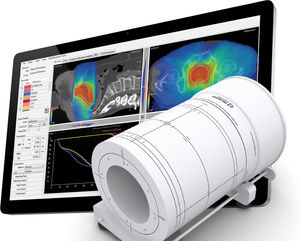

... Control Controles para impulsar una atención al paciente personalizada con más eficiencia Aproveche las ventajas de IMRT, VMAT y un colimador dinámico con RapidArc Dynamic. Genere planes de tratamiento de alta calidad de manera ...

... Defina fácilmente las secuencias de prueba que le permitirán realizar un control de calidad ampliado del acelerador para IMRT y VMAT en tan solo unos minutos. Compruebe la estabilidad con gran precisión y análisis detallados Constancia ...

... La radioterapia cambia constantemente, por lo que debemos adaptarnos. Antes del tratamiento Verifique la entrega de un plan preciso. Los análisis e informes se generan automáticamente. Se enviarán alertas si se activan por tolerancias ...